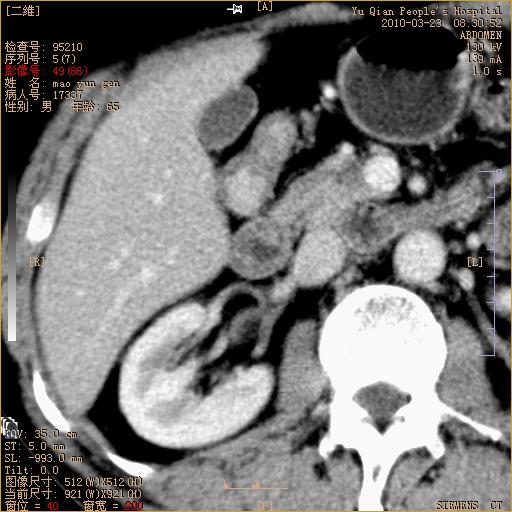

标题: CT25266:消瘦月余,前来肝部检查,请看看肠腔 [打印本页]

标题: CT25266:消瘦月余,前来肝部检查,请看看肠腔

肝区结肠占位,腺癌可考虑,建议肠镜活检。

升结肠肠壁增厚,不均强化,考虑升结肠腺癌可能性,建议肠镜检查。

1)考虑升结肠癌。2)右肾小囊肿。